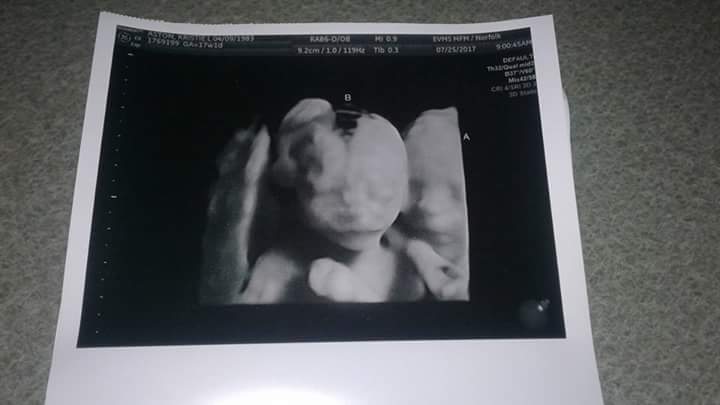

- Ultrasound Photos at 17 Weeks Pregnant With Twins

Ultrasound Photos at 17 Weeks Pregnant With Twins